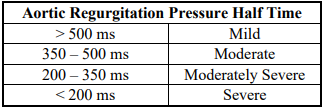

Pressure Half-Time by Continuous-Wave Doppler

o Mild (flat) = greater than 500 milliseconds

o Severe (steep) = less than 200 milliseconds

• Pressure half-time greater than 500 milliseconds

• Pressure half-time less than 200 milliseconds

AI PHT

AO PHT (ms)

mild

moderate

severe

mild

>500 ms

moderate

500 - 350 ms

350 - 200 ms

severe

< 200 ms